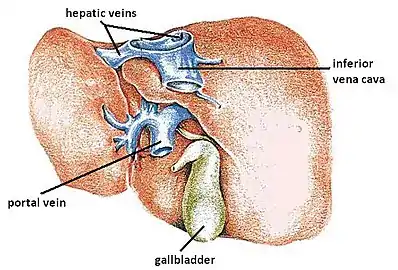

The hepatic veins are the veins of the liver, two of which are shown in this diagram. | |

In human anatomy, the hepatic veins are the veins that drain venous blood from the liver into the inferior vena cava (as opposed to the hepatic portal vein which conveys blood from the gastrointestinal organs to the liver[1]: 1212 ). There are usually three large upper hepatic veins draining from the left, middle, and right parts of the liver, as well as a number (6-20) of lower hepatic veins.[2] All hepatic veins are valveless.[3]

All the hepatic veins drain into the inferior vena cava. The hepatic veins are divided into an upper and a lower group.[2]

The upper group consists of three hepatic veins[2] - the right, middle, and left hepatic veins[1]: 1212 - draining the central veins from the right, middle, and left regions of the liver and are larger than the lower group of veins.[2] The veins of the upper group drain into the suprahepatic part of the inferior vena cava (i.e. part superior to the liver).[1]: 1212